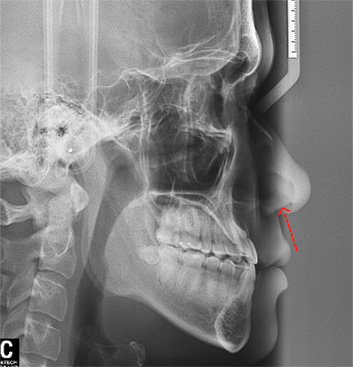

위턱에 비해 아래턱이 크고 전방에 위치, 우측으로 변위된 비대칭을 보입니다.

비 수술교정치료 이후 제대로 물리지 않던 어금니와 앞니 배열이 정상적으로 돌아왔습니다.